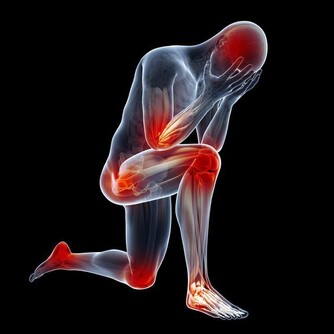

最常見的就是腰部疼痛,這種疼包括絞痛或者鈍痛,不要總認為腎結石的疼痛總是很劇烈,當結石還沒有下落到輸尿管的時候,所導致的疼痛往往不會非常劇烈。

除此之外,結石可能會損壞腎的微小血管,造成血尿,某些人還會表現為尿頻、尿急和尿痛等。